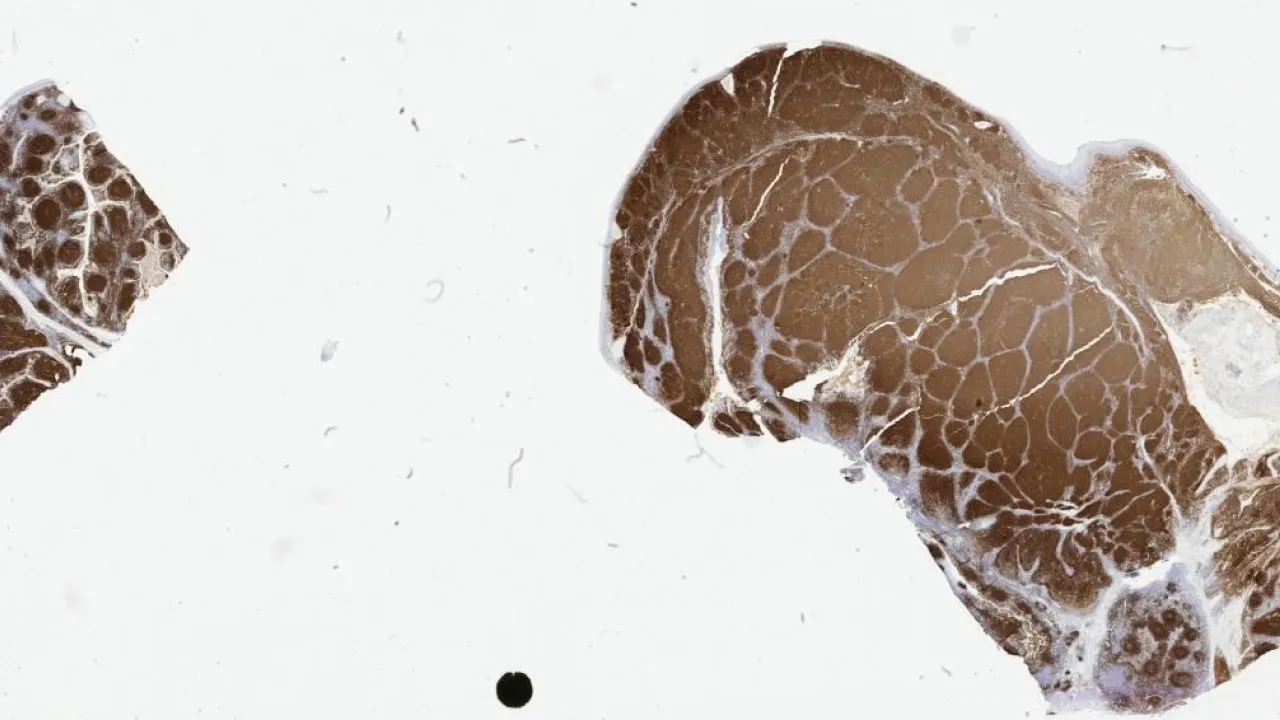

Bone Marrow, systemic mastocytosis, tryptase stain